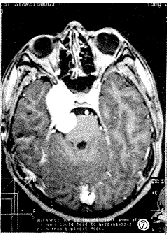

图5 同图4病例,横轴位T2加权像显示肿瘤呈较均匀高信号。

图6 同图4病例,注射Gd-DTPA后横轴位T1加权像显示肿瘤实性部分呈均匀强化,囊性部分呈环状强化。